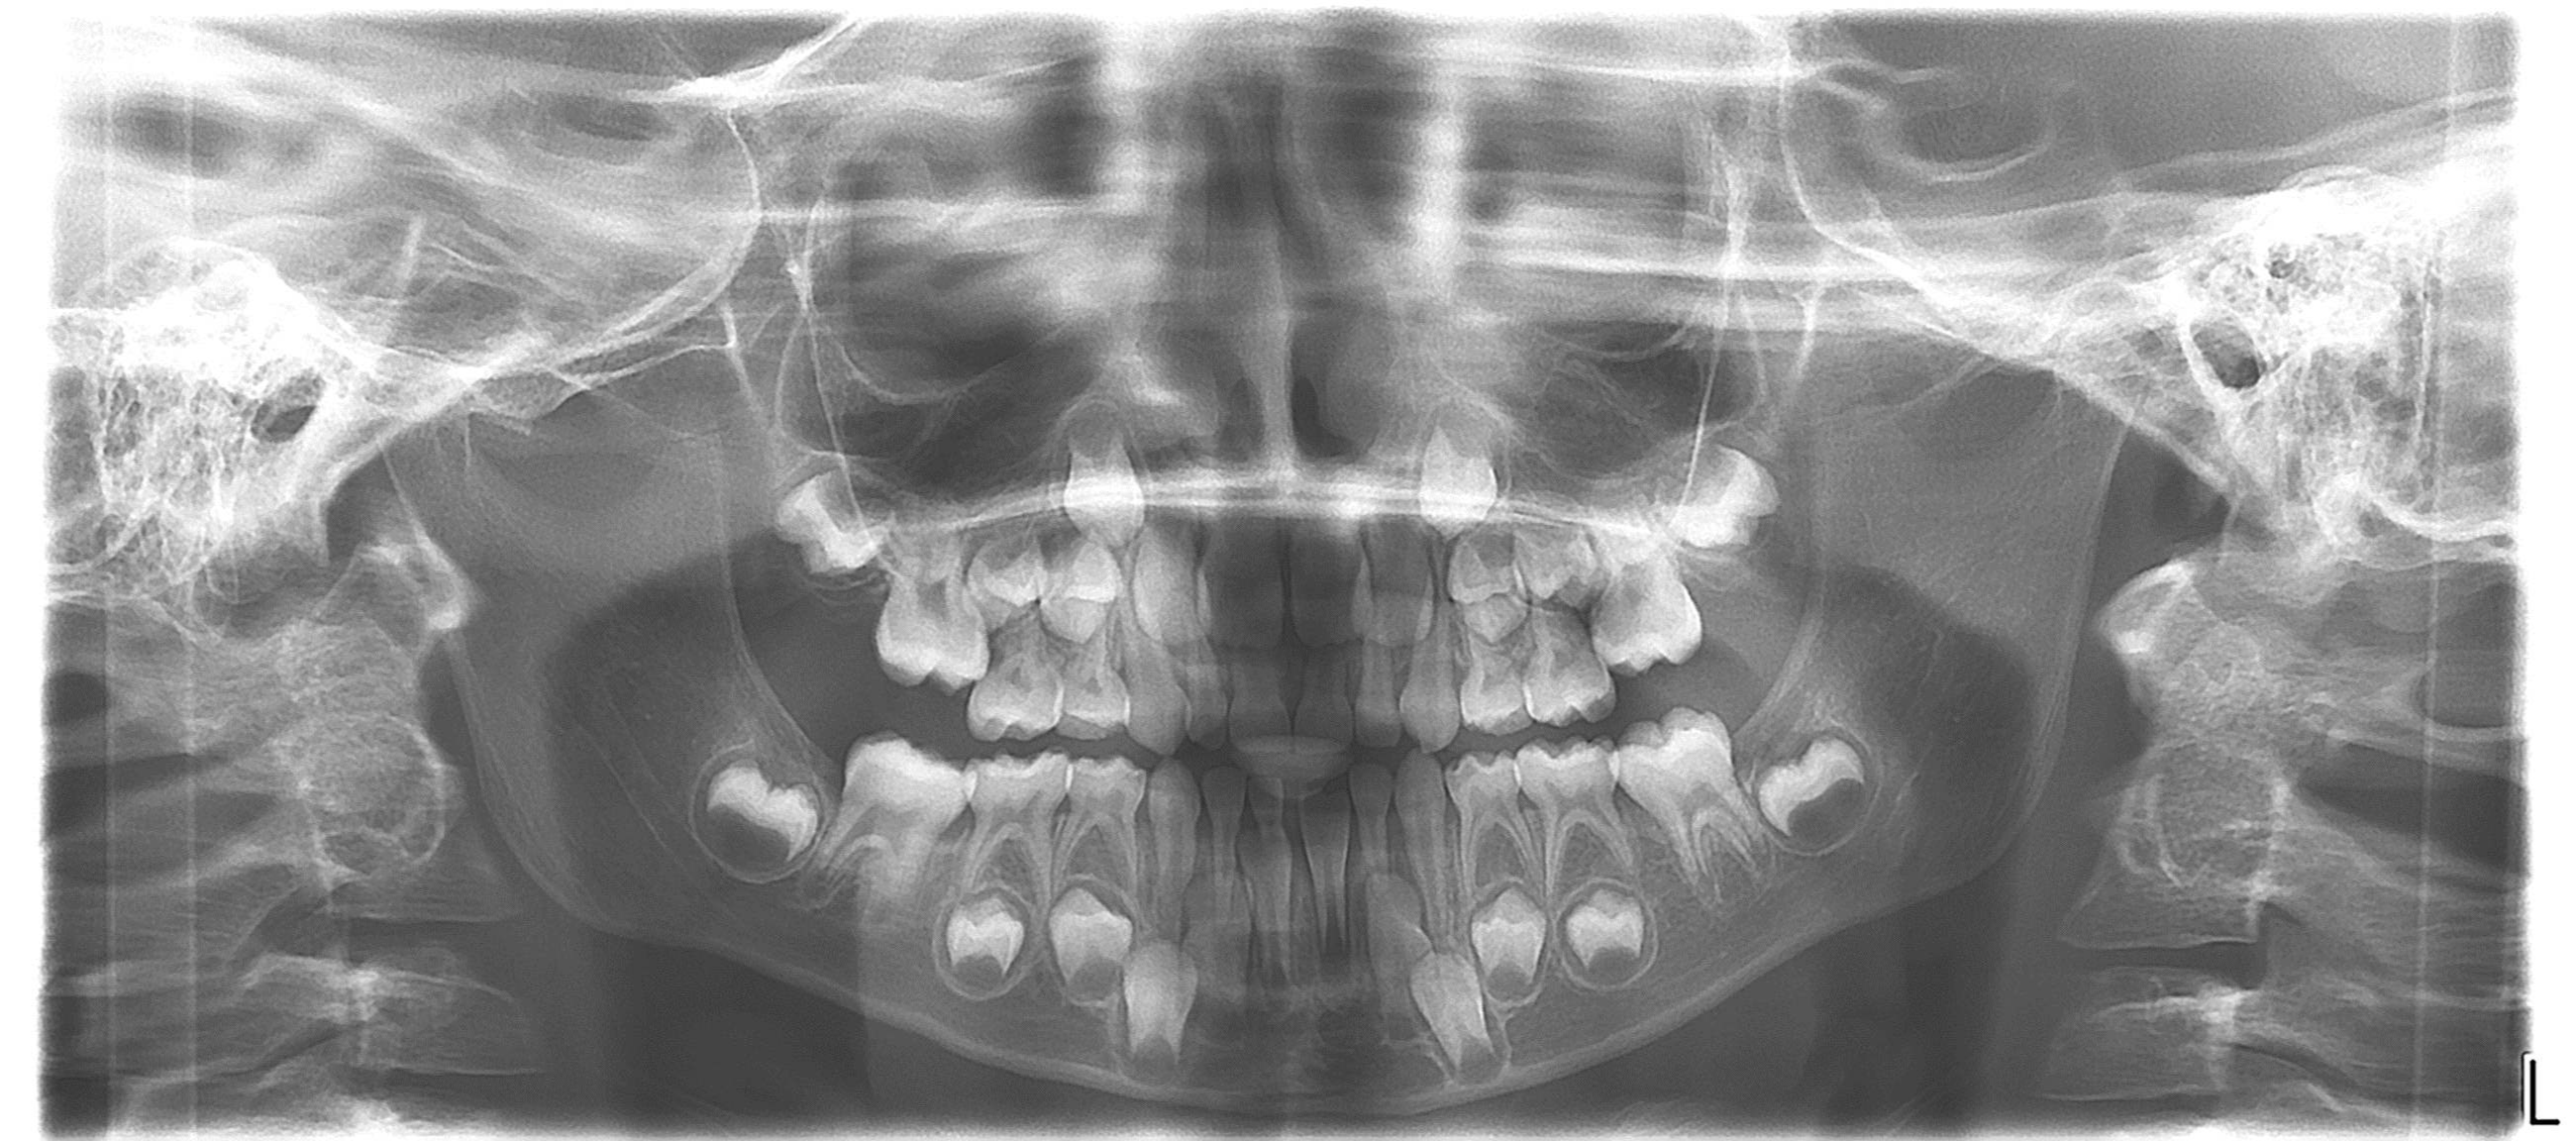

bilan début et en cours de traitement

bilan des radiographies début et en cours de traitement